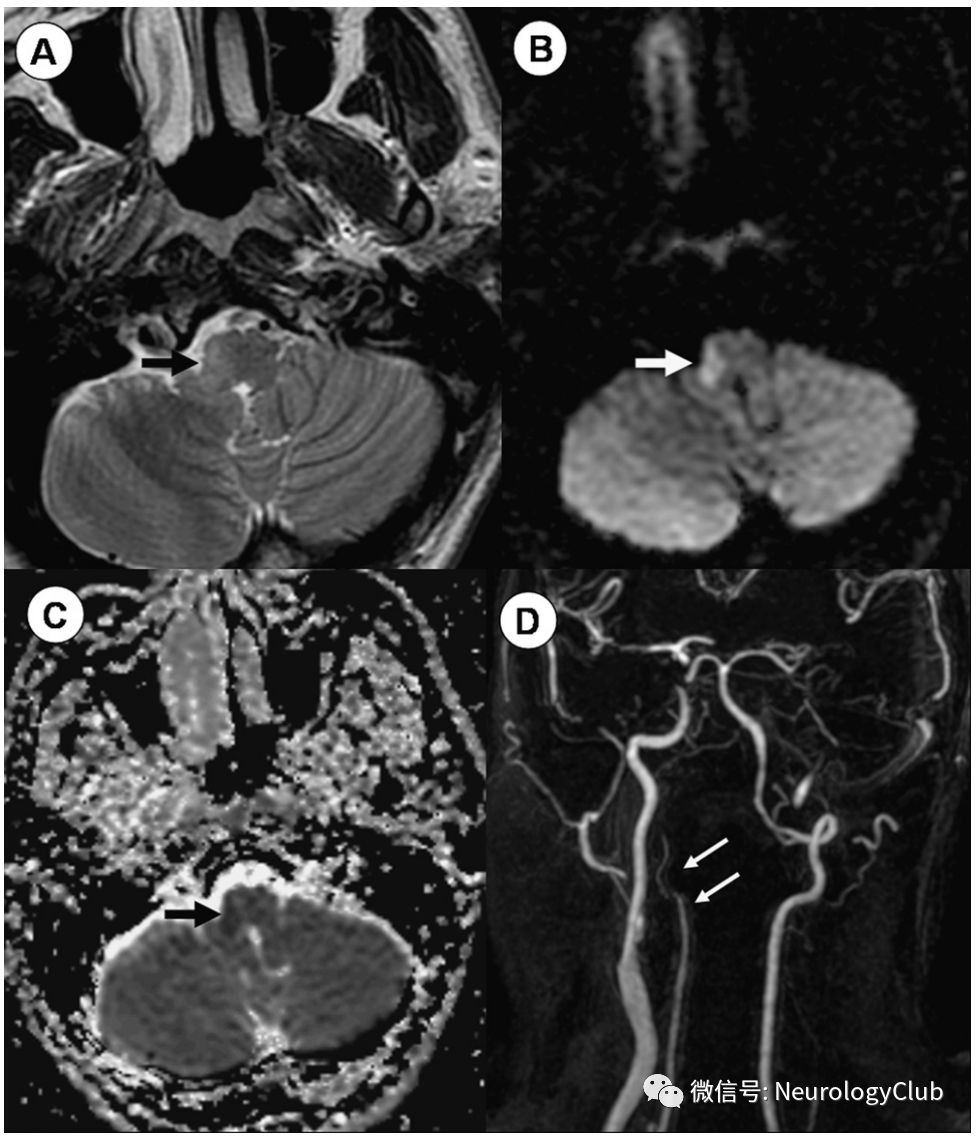

延髓外侧梗死(LMI,Wallenberg综合征)

患者可表现为同侧声音嘶哑和软腭瘫痪,同侧面部感觉缺失,同侧Horner综合征(眼睑下垂,瞳孔缩小,无汗),同侧共济失调以及同侧面部和对侧躯干痛温觉缺失(图3)。此外还可:有眼球震颤,眩晕,恶心和复视。常因椎动脉(75%)、小脑后下动脉(10%)以及基底动脉血栓形成所致。

图3:Wallenberg综合征;46岁女性患者,表现为交叉性感觉障碍、Horner综合征、眩晕、复视、共济失调、恶心和吞咽困难;A:T2WI可见右侧延髓外侧高信号病灶;B-C:DWI和ADC证实为急性梗死;D:MRA提示右侧椎动脉夹层